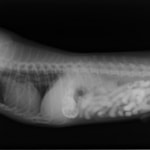

主訴:2日前の夜に桃の種を飲み込んだとのこと。元気・食欲に問題はなく、嘔吐などの消化器症状もみられなかった。誤飲した当日に他院にて催吐処置を試みたが、吐き戻さなかったとのこと。

単純レントゲン検査:明らかな異常所見なし

消化管バリウム造影レントゲン検査:胃内にて異物の存在を疑う異常所見を認めた。

造影直後